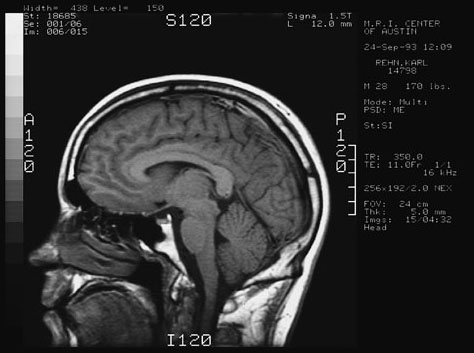

Here are 4 views taken from the MRI of my head.